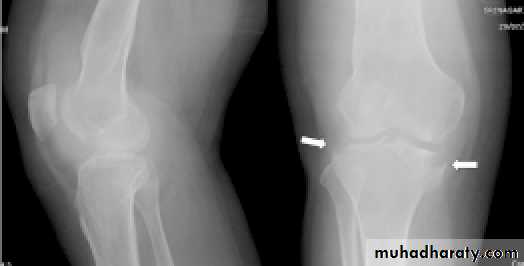

Imaging:

Pain x-ray:Priarticular osteoporosis,

Bone erosion and cystic lesion (on either sides of the joint) with little or no periosteal reaction, and

Progressive narrowing of joint space (phemister triad).